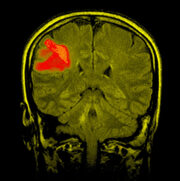

Molekulare Diagnose des primären ZNS-Lymphoms im Jahr 2024

In „The Lancet. Haematology“ beschäftigt sich ein Viewpoint-Artikel mit der molekularen Diagnose des primären ZNS-Lymphoms (PCNSL) unter Verwendung von MYD88Leu265Pro und IL-10.